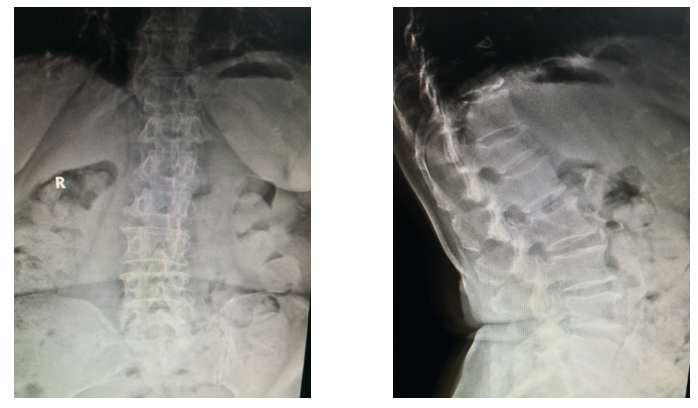

术前X片

术前X线

俯卧过伸位片